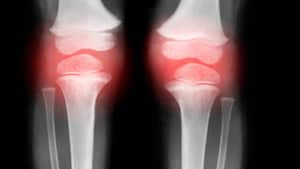

- Osteoporosis y fracturas compresivas.

- Problemas en las articulaciones, como la artritis.